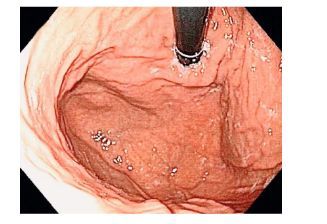

Trong quá trình nội soi tiêu hóa, khi đưa quan sát các phần của dạ dày ở tư thế máy thẳng, bác sĩ nội soi sẽ quặt ngược dây soi để khảo sát các vùng của đáy vị, tâm vị dạ dày, khi đó, sẽ quan sát được hình ảnh các nếp niêm mạc hội tụ tại chỗ nối thực quản – dạ dày, đó là nếp van thực quản – dạ dày.

Đặc điểm của NVDD-TQ theo phân độ Hill được đánh giá như hình 1. (A) Độ I: nếp gấp rõ, lỗ tâm vị ôm chặt ống soi. (B) Độ II: nếp gấp còn rõ nhưng không bằng độ I, lỗ tâm vị mở ra đóng vào nhanh theo hô hấp. (C) Độ III: nếp gấp không rõ và lỗ tâm vị không ôm chặt ống soi. (D) Độ IV: không còn nếp gấp, vùng nối dạ dày thực quản mở và có thể thấy được biểu mô thực quản ở tư thế quặt ngược ống soi ở dạ dày.

(A) Độ I: nếp gấp rõ, lỗ tâm vị ôm chặt ống soi. (B) Độ II: nếp gấp còn rõ nhưng không bằng độ I, lỗ tâm vị mở ra đóng vào nhanh theo hô hấp. (C) Độ III: nếp gấp không rõ và lỗ tâm vị không ôm chặt ống soi. (D) Độ IV: không còn nếp gấp, vùng nối dạ dày thực quản mở và có thể thấy được biểu mô thực quản ở tư thế quặt ngược ống soi ở dạ dày.